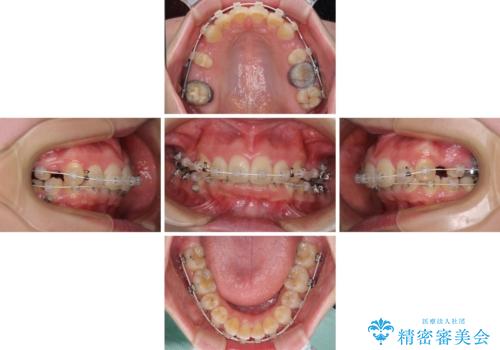

上顎前突を改善するために上顎左右第一小臼歯を抜歯し、補助装置を用いて上顎臼歯が前方に移動しないように工夫しながら、表側のワイヤー装置にて歯列を整えていくこととしました。

予想通りに治療は困難を極め、その上途中来院されない時期があったため、非常に長期間に及びましたが、周囲の方々が驚愕するほど口元の印象を改善することができました。